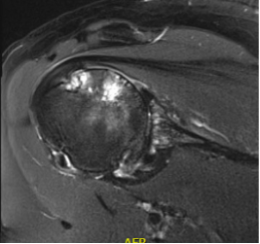

BH is a right hand dominant 70-year-old female, who is retired and moderately active. She presents with 8 months of progressively worsening left shoulder pain affecting her ADLS, sleep and recreational activities. She is 10 years s/p a right anatomic total shoulder arthroplasty. Radiographs and advanced imaging reveal glenohumeral joint advanced degenerative joint disease with an intact rotator cuff. Preoperative planning reveals a native 3 degrees of retroversion with 0 degrees of inclination. As she was extremely happy with the fully functional contralateral shoulder she has enjoyed for the past decade, she was interested in the same solution – an anatomic total shoulder arthroplasty.